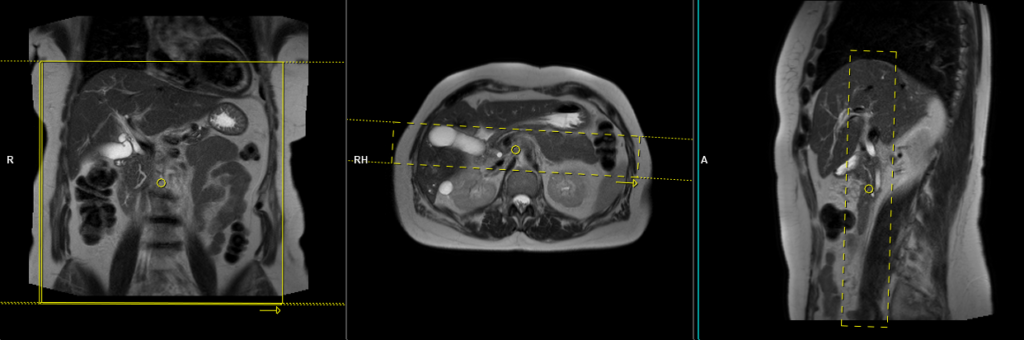

T2 HASTE thick 40mm breath hold coronal oblique(radial)

Plan the coronal radial thick slab slices on the axial HASTE sequence. Position the center of the block over the common bile duct . Verify the positioning in the other two planes. Establish an appropriate angle in the sagittal plane, aligning it horizontally across the bile duct. Ensure that the slices adequately cover the entire common bile duct and pancreatic duct. Use phase oversampling to prevent wrap-around artifacts. Instruct the patient to hold their breath during image acquisition.

Parameters

TR 4000-5000 | TE 500 | FLIP 150 | NEX 1 | SLICE 40MM | MATRIX 320X320 | FOV 300-400 | PHASE R>L | OVERSAMPLE 50% | IPAT ON |